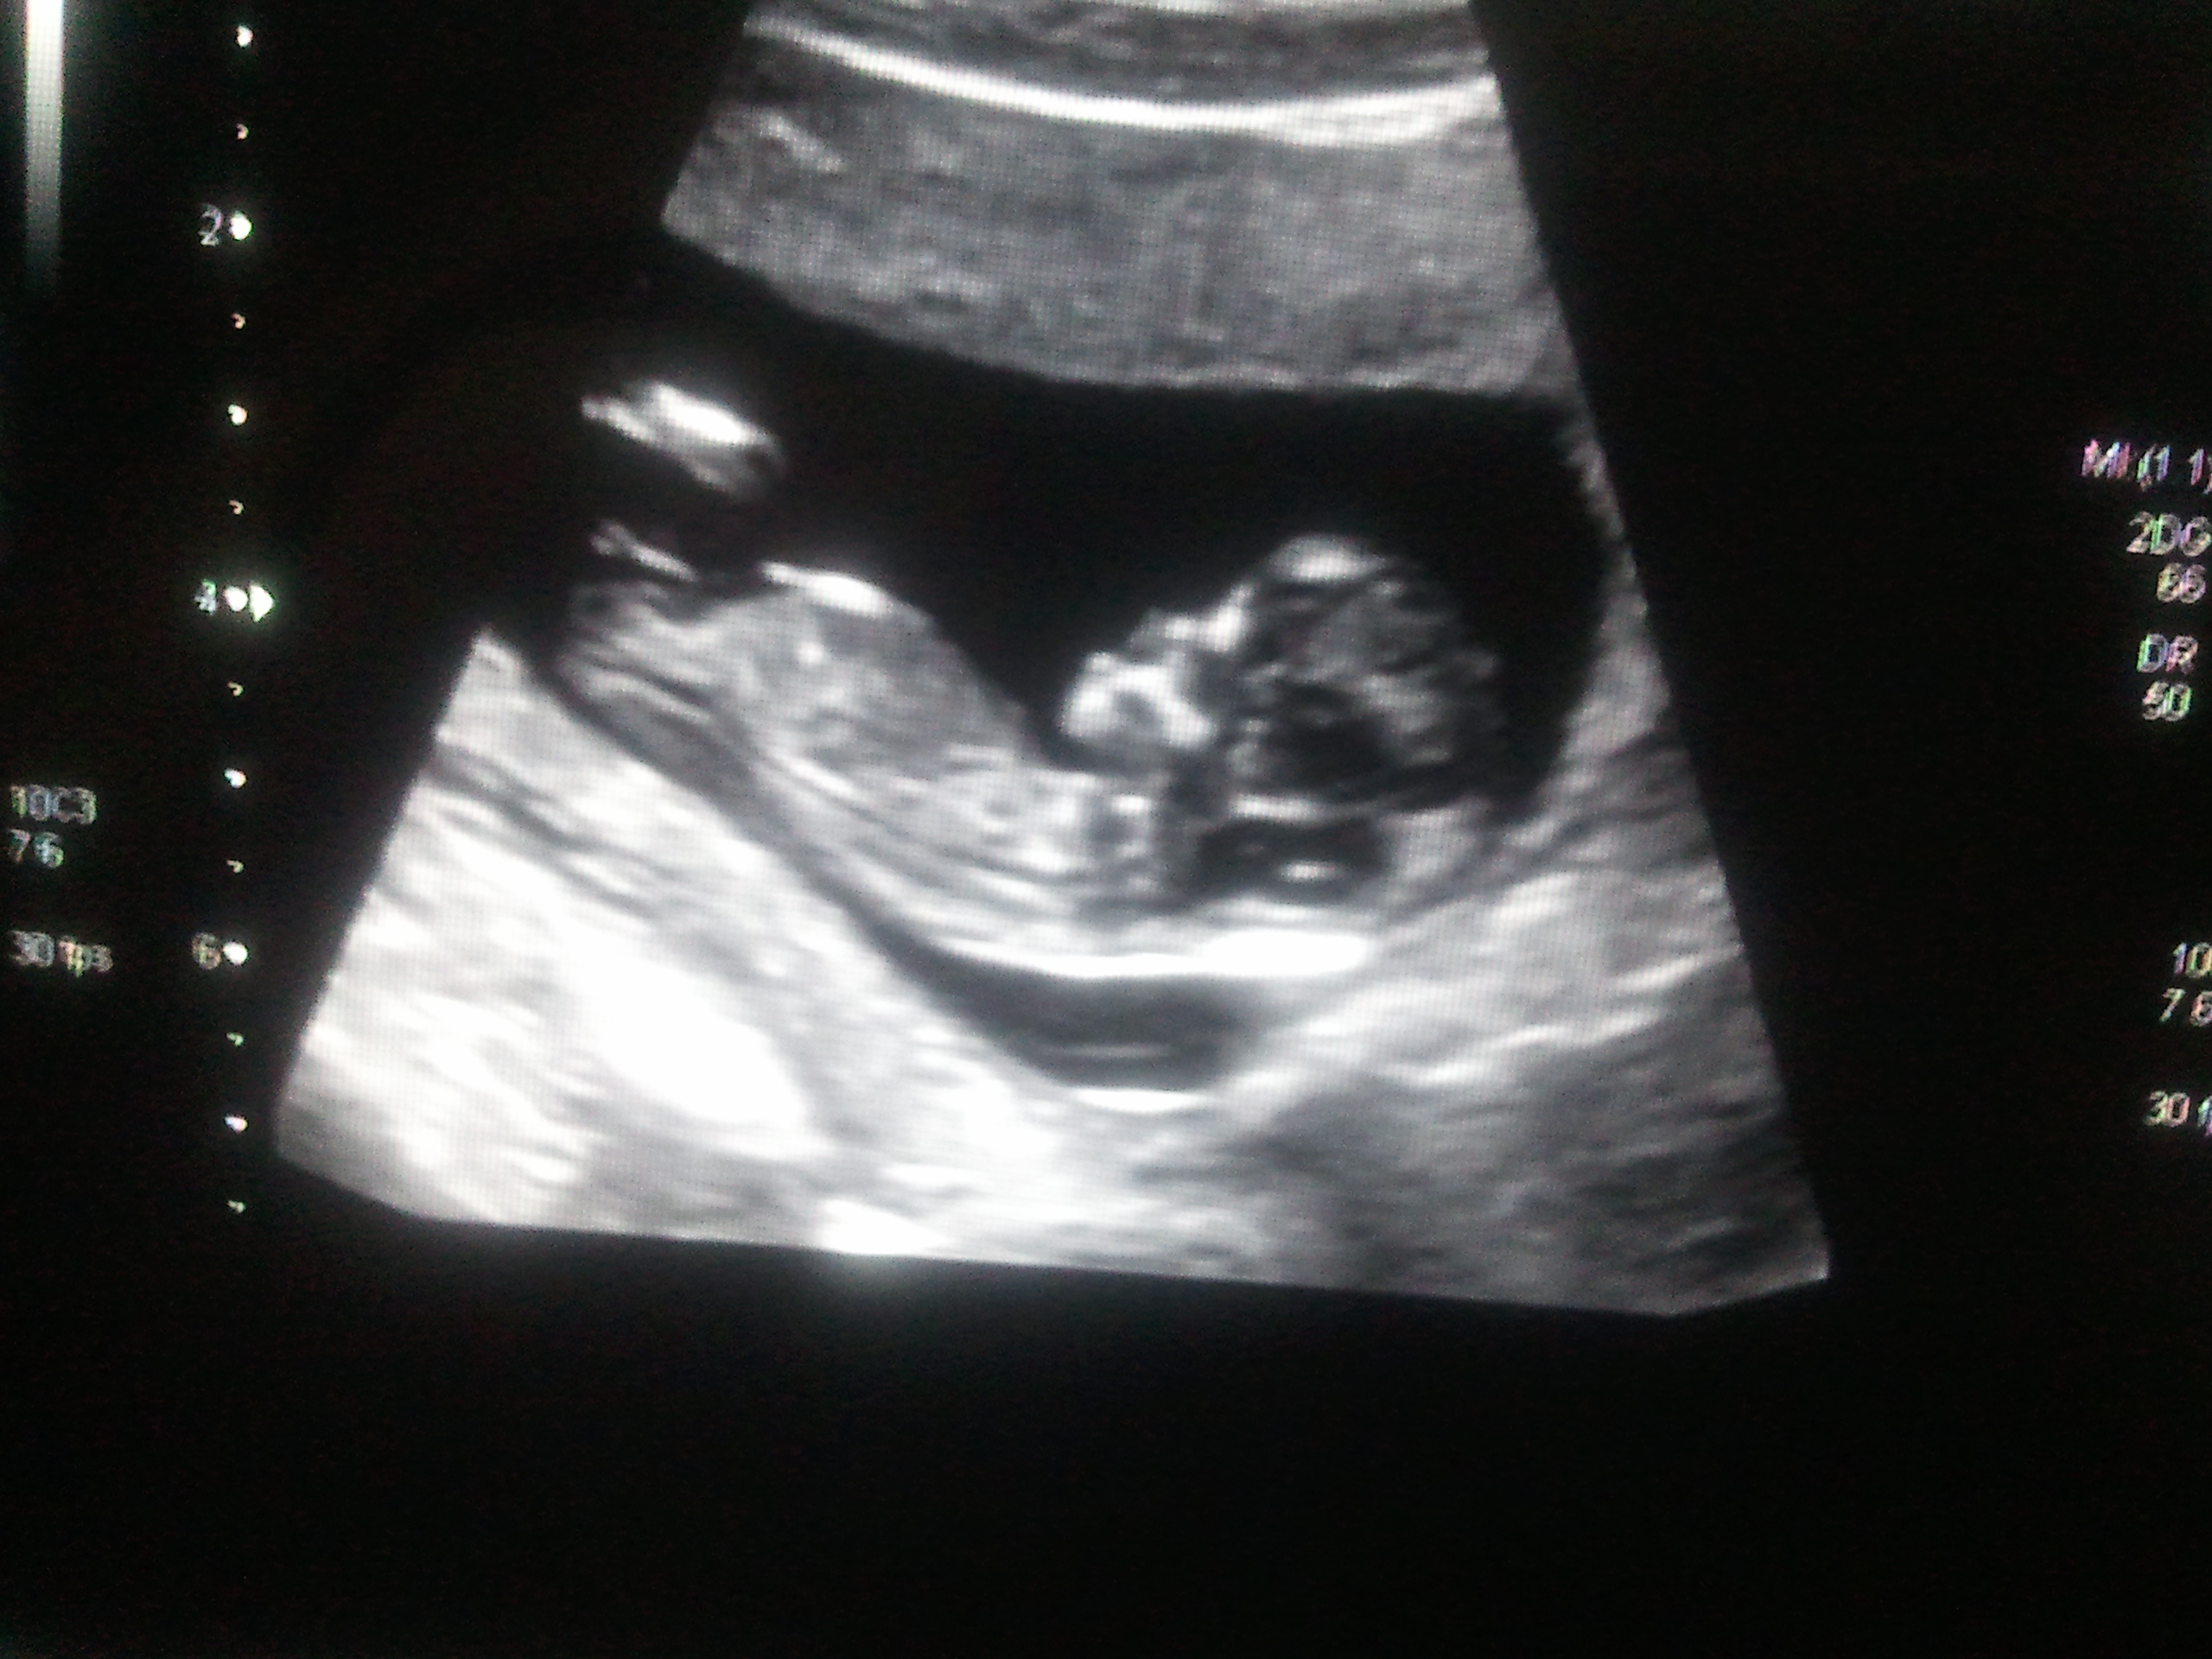

This is a clearer image I found taken at what we THOUGHT was 12w 4d but have just found out its only 11w 4-5d... does this mean its now 50/50? :( Attachment 1551